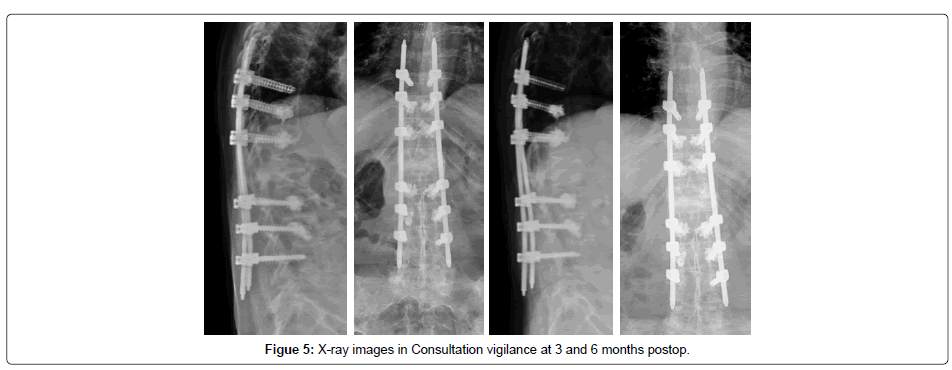

This patient was submitted in February 2016 to the percutaneous transpedicular fixation of D10-D11-D12-L2-L3-L4, with cemented screws. She refused surgery by anterior approach with L1 corpectomy and “cage” placement.

The postoperative period was uneventful, having started deambulation with Jewett’s orthosis. Five months after surgery, there was a clear improvement in painful complaints and no need to wear the vest. Signs of neurological damage were never objectified. Postoperative radiographs demonstrate a frank improvement of the kyphotic angle (37) and the vertical sagittal axis (12.9 centimeters). The control CT scan performed in November 2016 revealed fracture with signs of progression for consolidation (Figure 1-7).